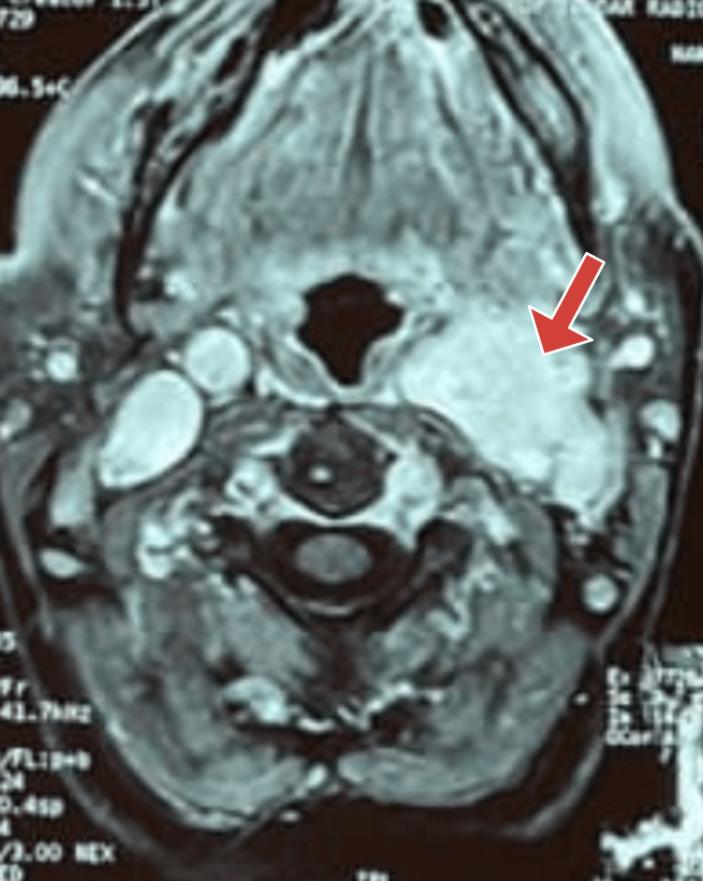

CT扫描显示,左颈动脉分叉处有一个异质性增强肿块,位于颈内动脉和颈外动脉之间(图1)。

图1 颈部CT扫描显示左颈动脉分叉处有一个软组织肿块(红色箭头)